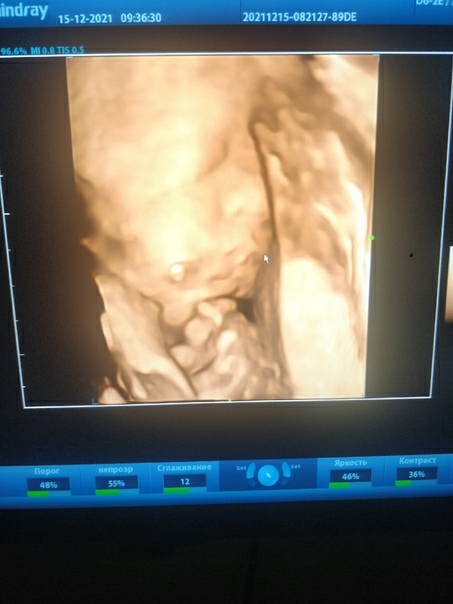

15.12.21 были на третьем скрининге. Всё хорошо, окончательно подтвердили, что будет сын (тот продемонстрировал все свои достоинства и отвернулся от датчика). Уткнулся лицом мне в бедро и всё, как хотите 😅 Если верить аппарату УЗИ, то весит уже кило девятьсот, врач прогнозирует, что к родам будет в пределах 3400-3800 🙈